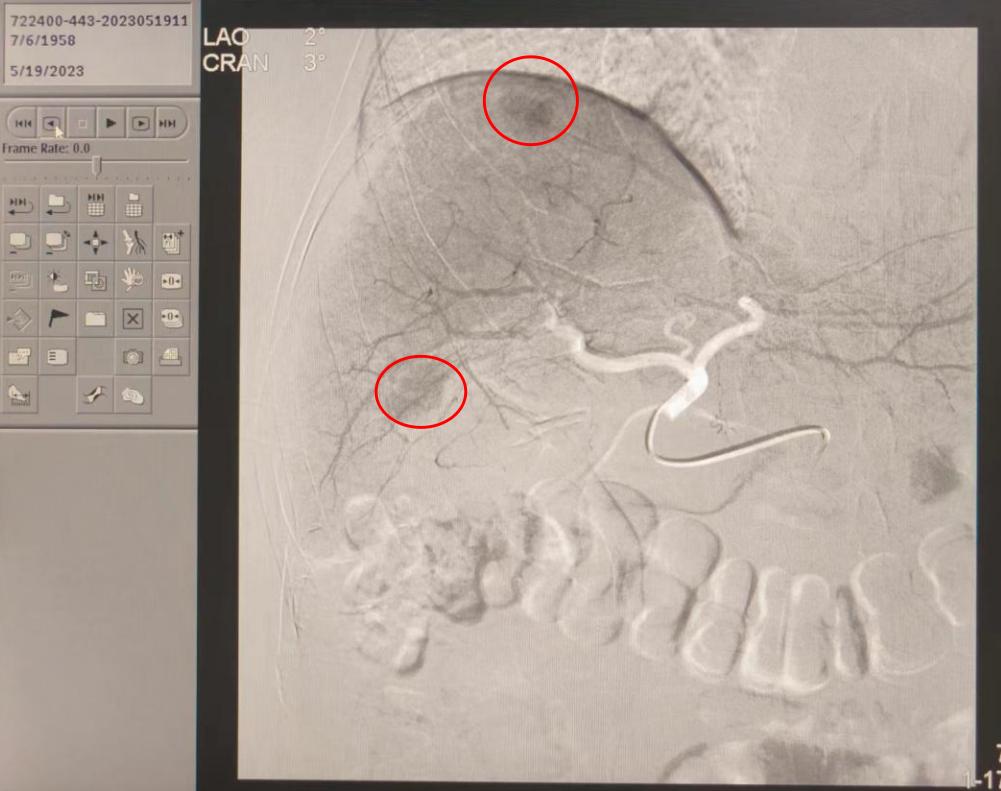

造影中(如下)

肝动脉造影结果显示:腹腔干动脉稍扭曲,肝动脉稍增粗,右肝上缘S8段可见一球形肿瘤染色区,右肝下缘S6段肿块状淡染色区,未见明显血管畸形及动静脉瘘。初步判断肝S8肿瘤染色区为肝癌病灶,肝S6肿块染色区为肝脏再生结节,肝癌的癌前病变可能。